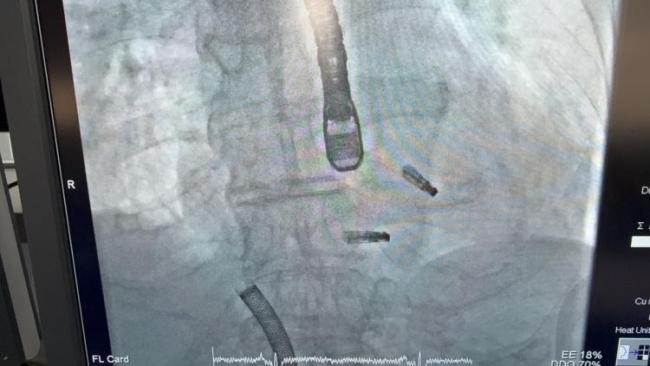

中国援赤几医疗队为一月龄婴儿实施多指畸形矫正术

人民网约翰内斯堡11月7日电(记者邹松)中国援赤道几内亚医疗队日前在马拉博地区医院顺利实施了一例特殊的手部矫形手术,为一名仅一月龄的当地婴儿切除双手先天性畸形多指,帮助其恢复正常手部形态与功能。此次手